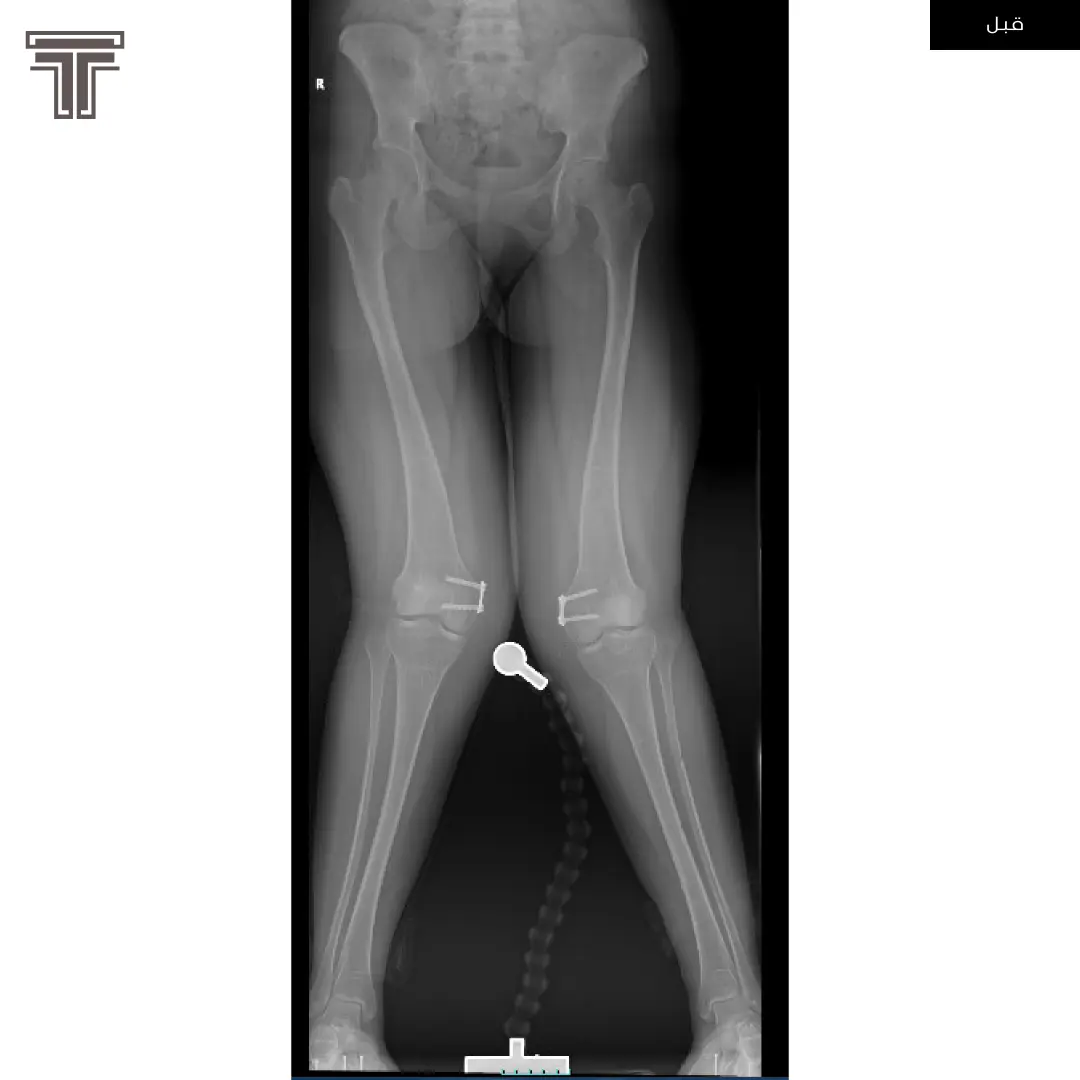

عندما تهمل خلوع الورك الولادية لعمر كبير يصبح علاجها وارجاعها صعب ويتطلب عملية استبدال للمفصل. وفي مثل هذه العمليات وتحديدا في استبدال مفاصل خلوع الورك الولادية يتطلب تقصير في طول الفخذ لتجنب المضاعفات.